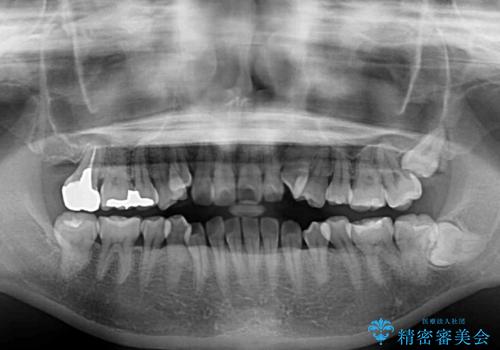

- 前歯のデコボコや八重歯の様になっていることを気にして来院された患者様です。

犬歯捻れて前方に飛び出しており、下顎前歯もそれに沿うようにデコボコとなっていました。

IPR(歯と歯の間を削る処置)によりスペースを獲得して上下顎前歯のデコボコを改善し、前歯が前方に突出しないように設定した上で、インビザラインにて矯正治療を行うこととしました。